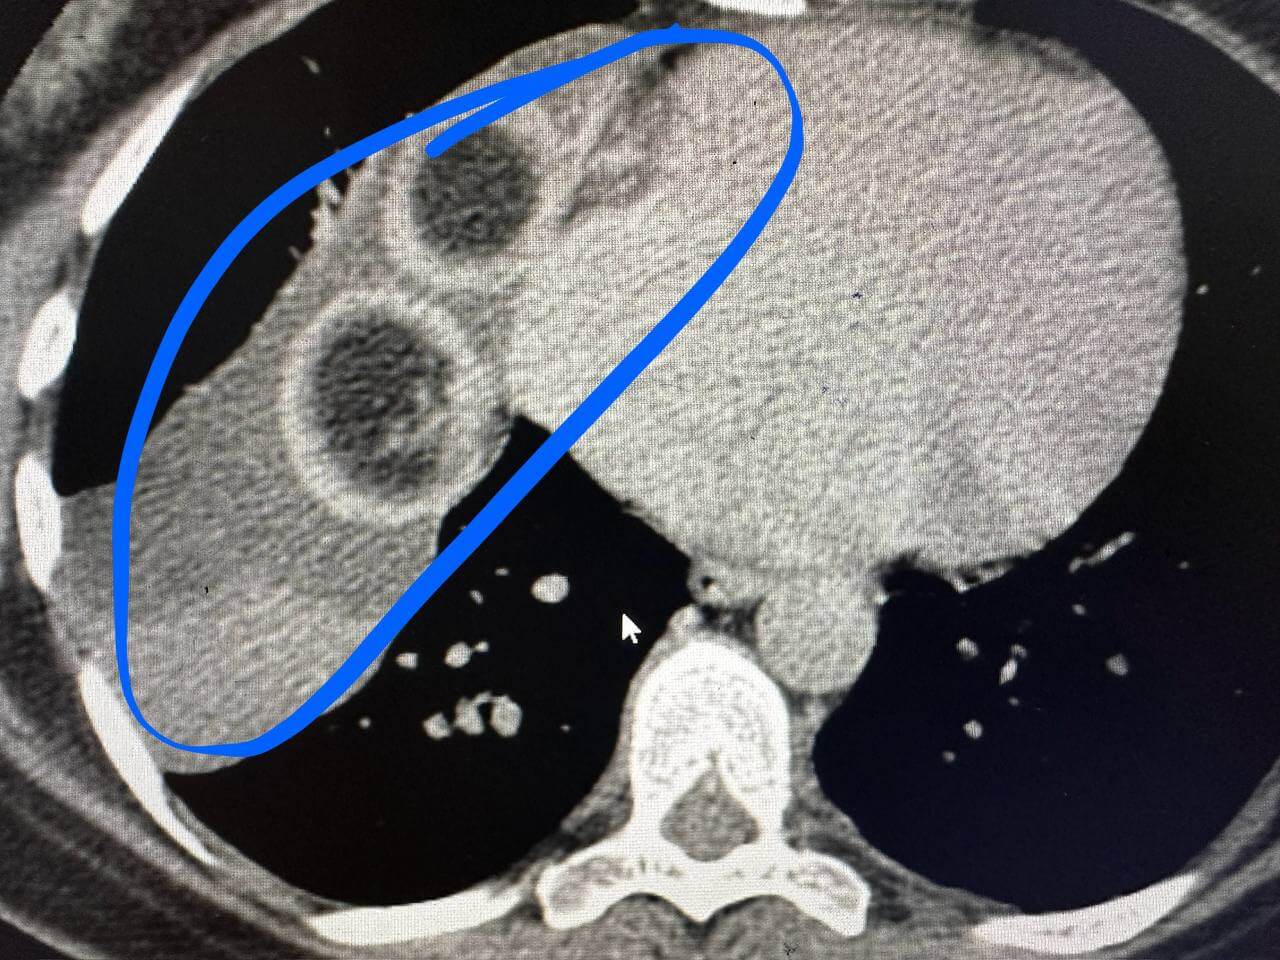

Образование заметили у 44-летней жительницы Бавлинского района республики на флюорографии, на КТ подтвердили. Киста расположилась в средостении – это центральное пространство грудной клетки между двумя плевральными полостями. Женщину направили в РКБ.

Оказалось, что рядом с сердцем выросла дермоидная киста размером 10 на 7 на 15 сантиметров. Внутри этой кисты образовались две большие волосяные головки.